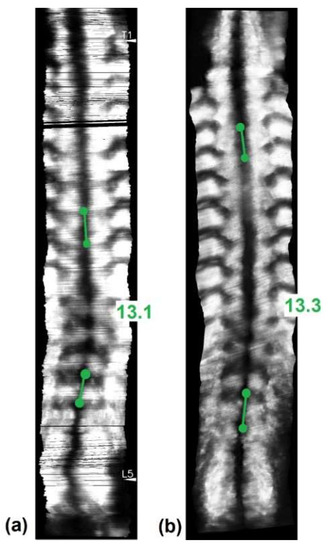

2.7. Angle Measurements and Study Design